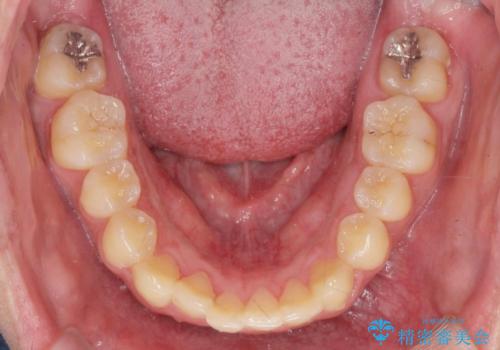

正中過剰埋伏歯で生じた前歯の審美障害 矯正治療での改善

- 前歯の見た目に悩まれて来院されました。

当初他院では、抜歯を行いセラミックブリッジを提案されていましたが、他の方法はないかと総合歯科治療を行う当院へと相談来院されました。

「時間がかかっても良いので、できれば歯を抜かずに矯正治療で治したい。」という強い希望があったので、矯正治療で歯並び・審美性の改善を計画します。